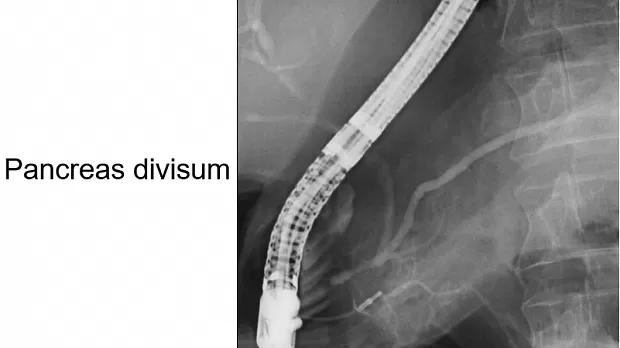

Pancreas divisum представляет собой аномалию раз­вития ПЖ, обусловленную нарушением слияния дор­сального и вентрального панкреатических зачатков. Результатом этого является раздельное дренирование двух частей ПЖ: вентральная часть головки дренирует­ся коротким вирсунговым протоком, открывающимся на большом дуоденальном соске, а секрет от дорсаль­ной части головки, а также тела и хвоста, оттекает че­рез санториниев проток и малый дуоденальный сосок. Pancreas divisum встречается у 5-10% населения и в боль­шинстве случаев не проявляется клинически [46]. В то же время имеется немало наблюдений, демонстрирую­щих ассоциацию между этой аномалией и острым ре­цидивирующим либо ХП. Предполагается, что в ряде случаев при выраженной стимуляции секреции ПЖ небольшие размеры малого дуоденального соска не по­зволяют обеспечить адекватный отток секрета от боль­шей части ПЖ, то есть возникает относительный сте­ноз, сопровождающийся повышением давления в пан­креатическом протоке, что, вероятно, и лежит в основе развития панкреатита [45]. Возможность такого пато­генетического механизма подтверждается улучшением состояния пациентов после проведения эндоскопичес­кой папиллосфинктеротомии малого дуоденального соска [46].